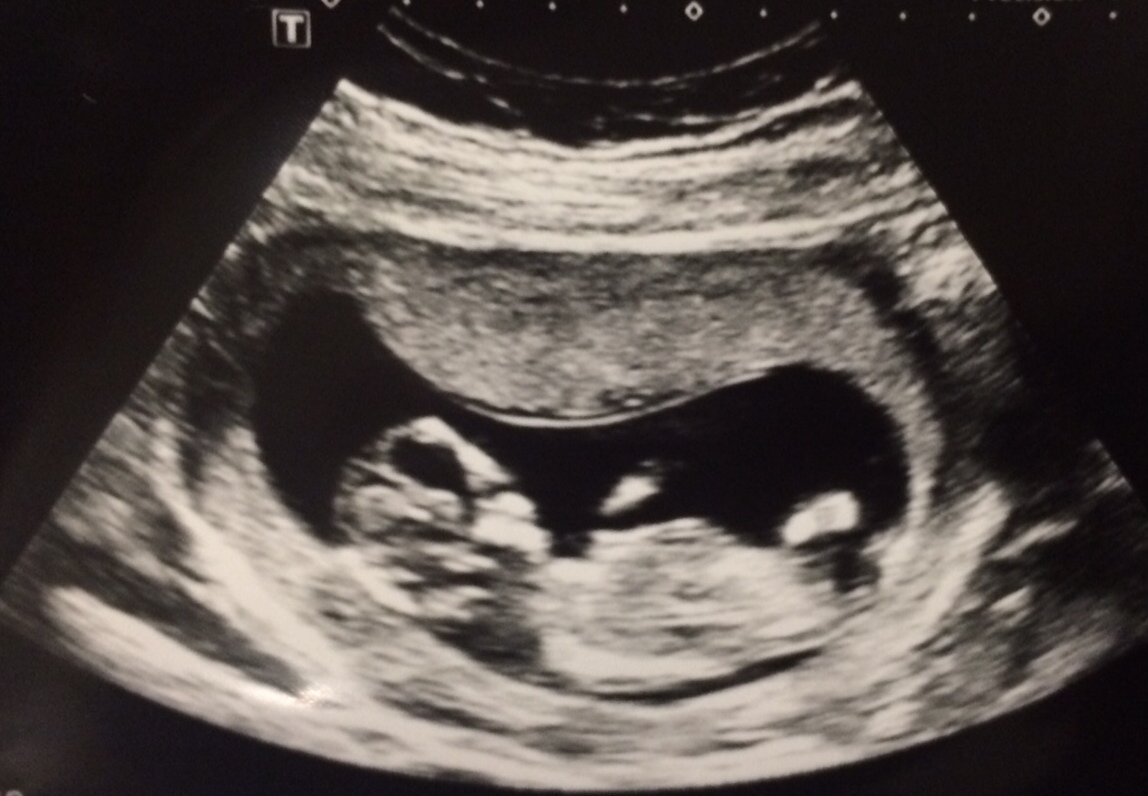

Please help gender predictions from 13 week US

Possibly girl

Maybe girl, more pics?